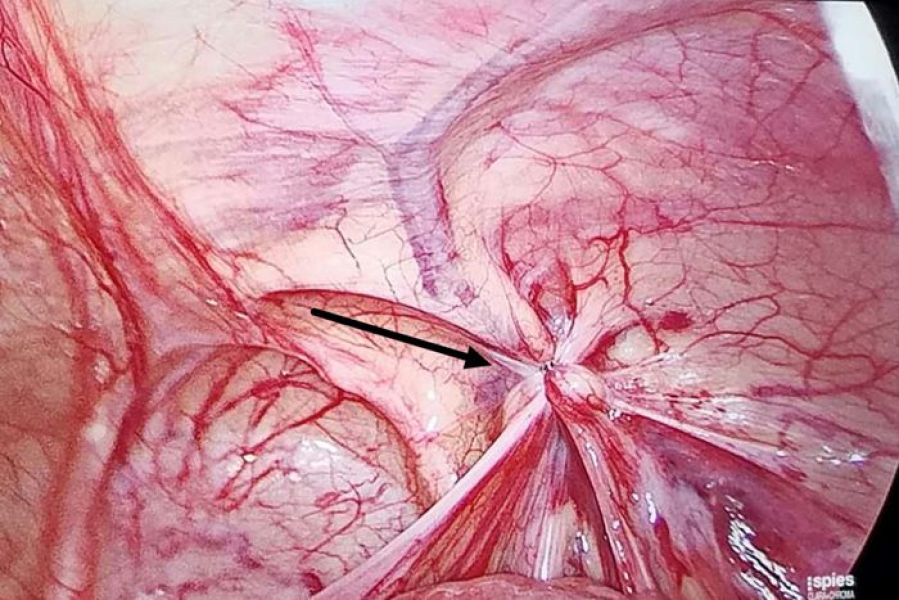

附图:

手术操作前所见

手术操作完成后所见(箭头所指为疝所在的内环口)